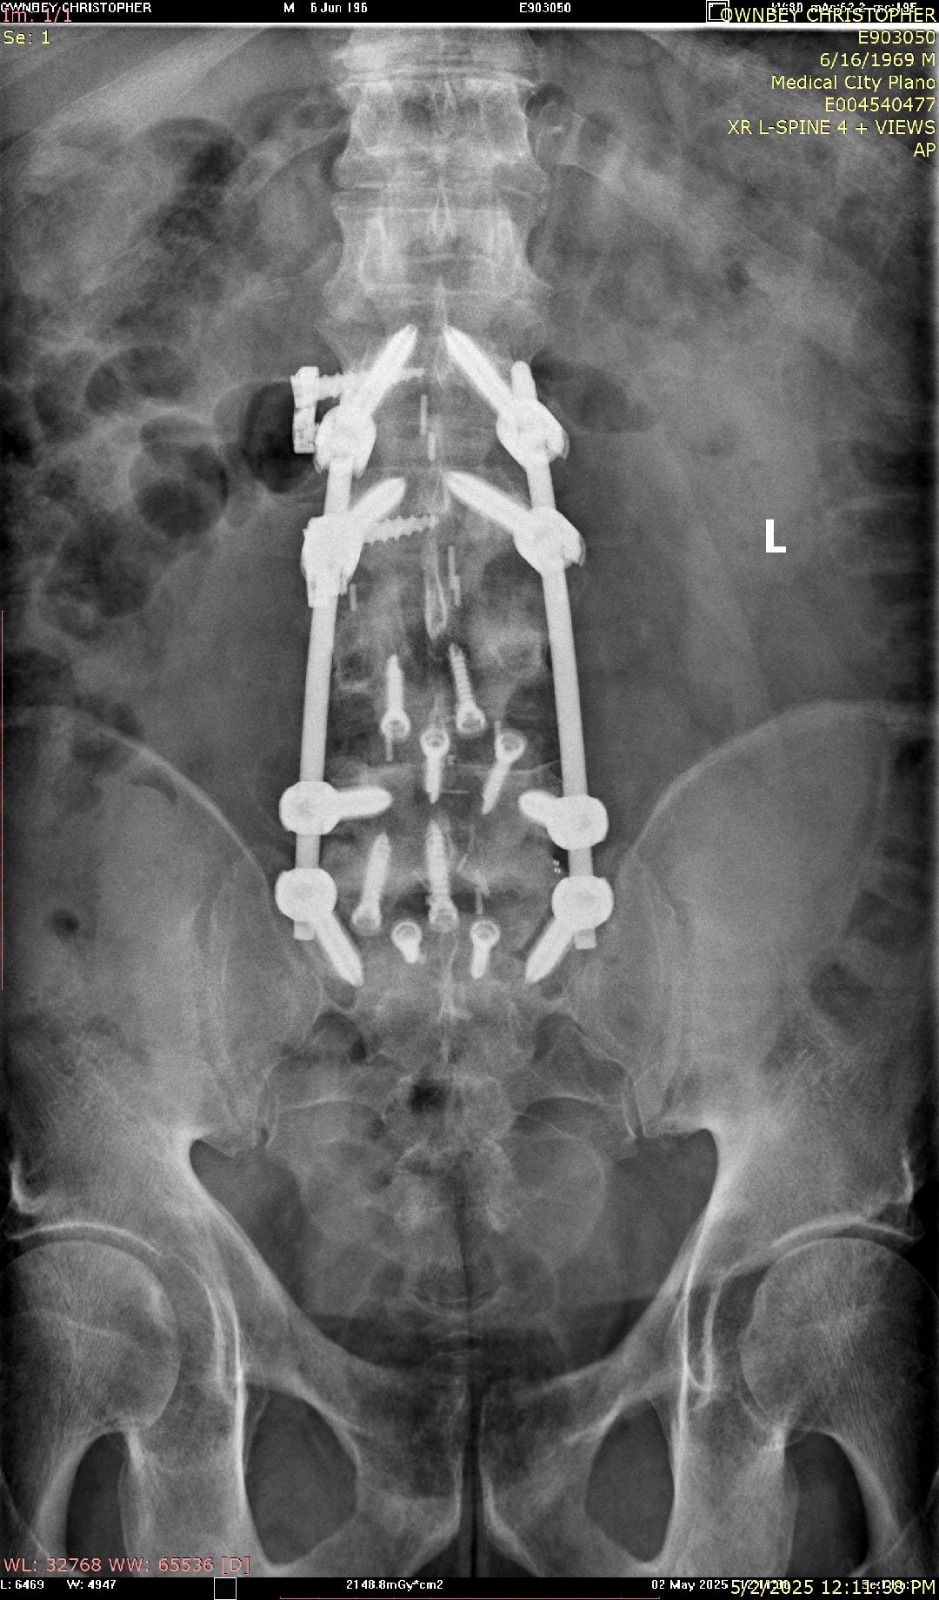

He’s fought through multiple back and neck surgeries, battled setbacks that would’ve stopped most people, and carried the responsibility of raising two boys 24 years apart, with two grandchildren depending on his example. Slowing down was never an option.

2024 was his year of full neck and back fusion — and his comeback.